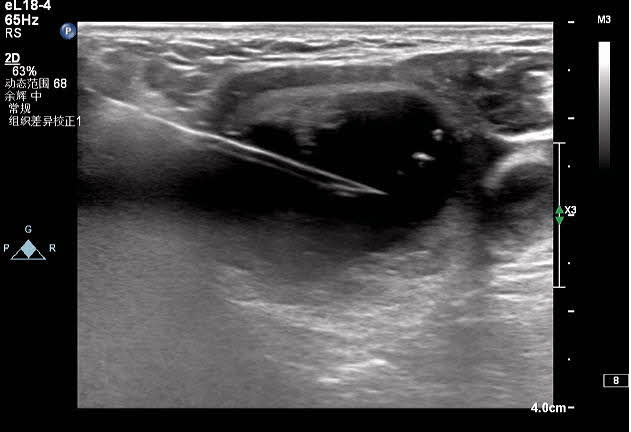

對(duì)結(jié)節(jié)的囊性部分進(jìn)行穿刺抽吸+聚桂醇反復(fù)沖洗